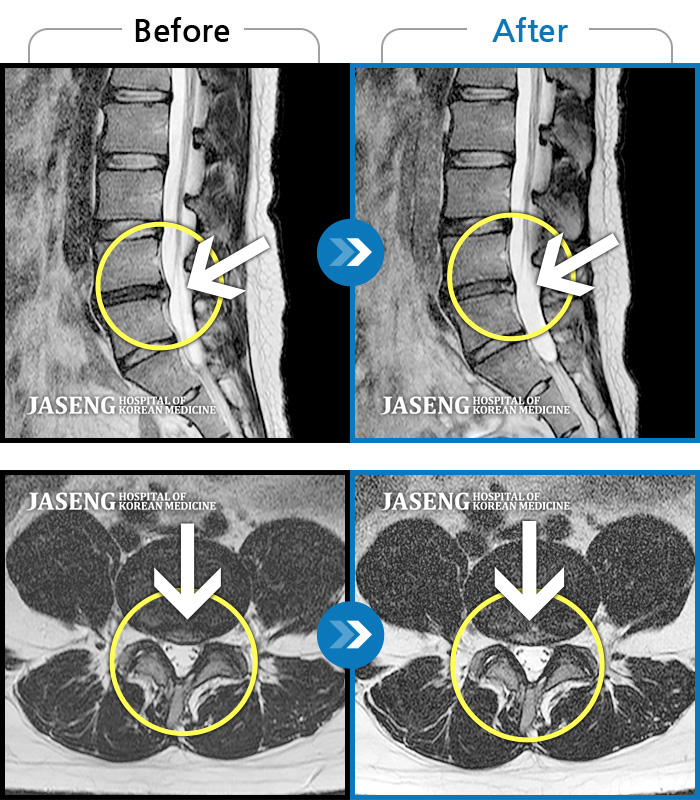

• 허리디스크